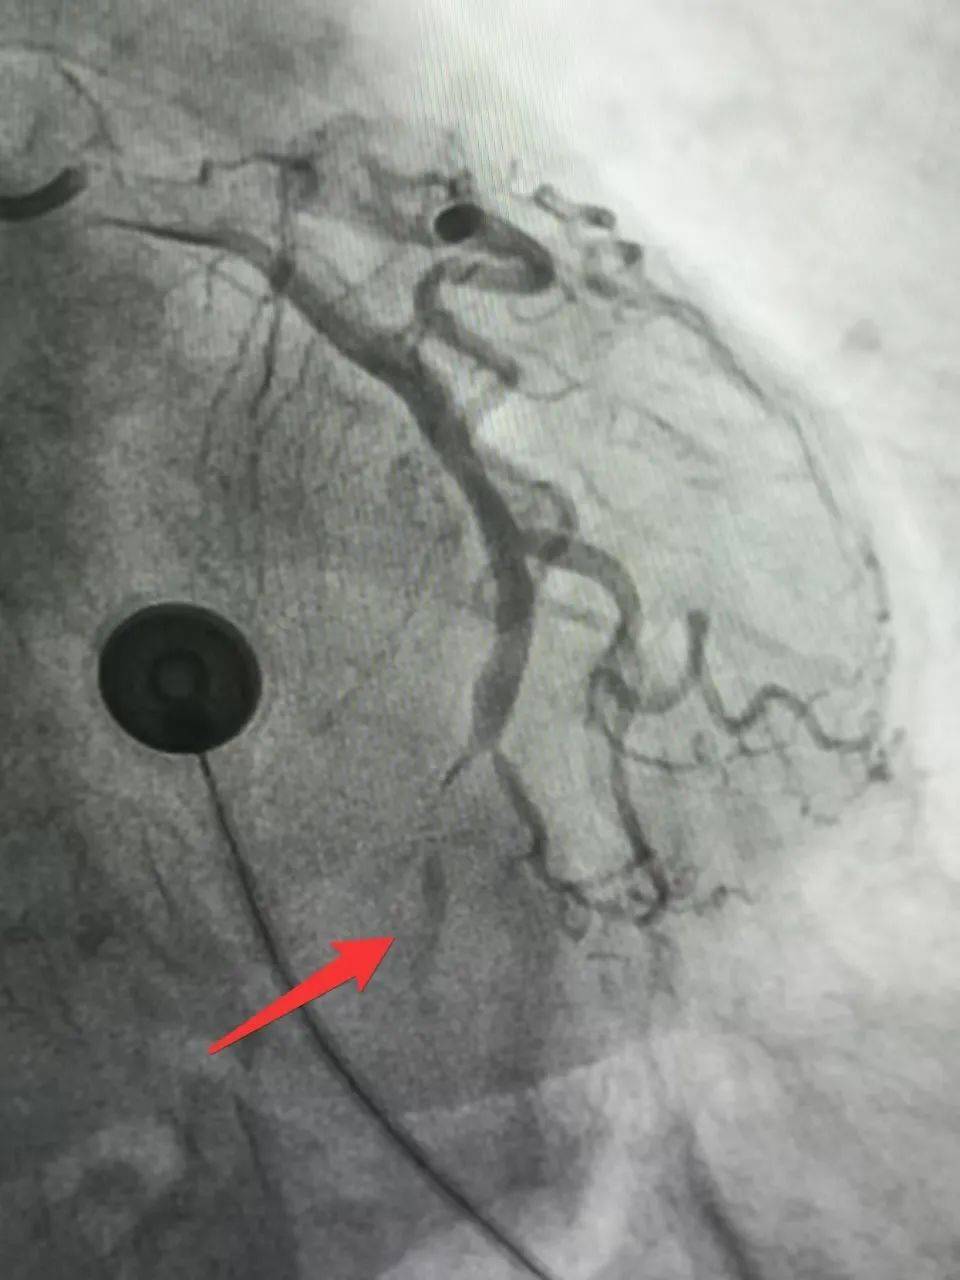

头晕、乏力竟是心梗“信号”!医生:7个非典型症状,警惕心脏问题